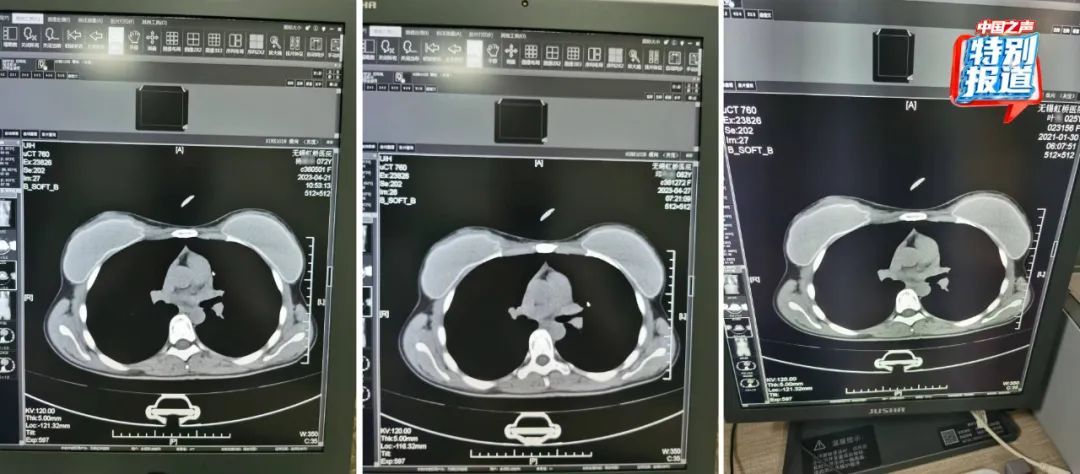

在被举报的病历中,杨某某(72岁)和邱某某(62岁)的病历里,有根据所拍片子的情况做出的诊断,却找不到对应的影像。6月份又查到了她们的CT影像,片子上清晰看出,两位患者的吊坠形状、大小和位置都基本一致。

不仅这两位患者CT影像类似,朱成刚比对发现,2021年做过CT的25岁女性叶某的片子上,也有看起来极为相似的吊坠,肉眼看,三人的片子几乎一模一样。

72岁的杨某某、62岁的邱某某与25岁的叶某,三人的片子几乎一模一样。